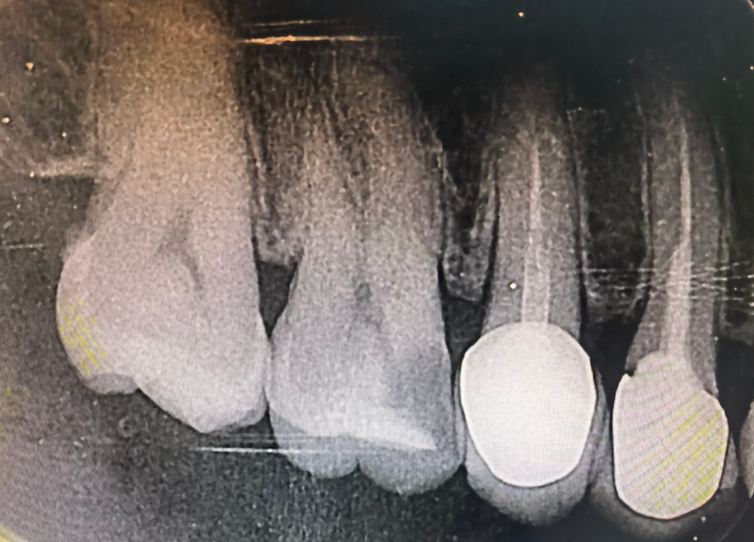

食物残渣和细菌在此地长期“安居乐业”,形成菌斑生物膜。它们产酸腐蚀牙面,从而引发邻面龋。这种蛀牙极具隐蔽性和欺骗性:从牙齿的正面看过去,可能仅仅是一条细微的黑线甚至完全看不见,但在X光片下,它可能已经在牙齿内部蛀成了一个巨大的“隧道”或“山洞”。等到出现疼痛症状时,蛀洞往往已经深及牙髓,需要进行复杂的根管治疗了。

图1: X光片示,左数第二颗牙(右上第一磨牙近中)的表面看似只有微小缺损,但其内部邻面已形成大面积龋坏洞,几乎穿透至牙髓。这就是邻面龋的典型特征——“口小底大”。